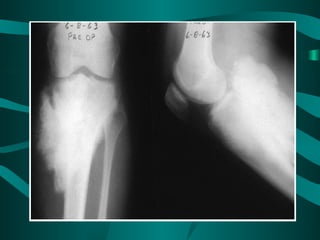

•    Classic X-ray findings:

1. Codman's triangle (periosteal elevation)

2. Sunburst pattern

3. Bone destruction

• Pathology:

– Often involves the metaphysic of long bones

– Usually around the knee (distal femur and

proximal tibia)

Classic X-ray findings: 1. Codman's triangle (periosteal elevation) 2. Sunburst pattern 3. Bone destruction